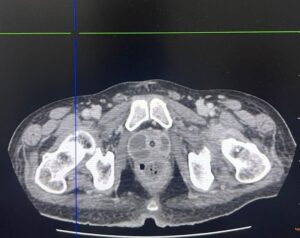

Tomografia computadorizada de abdome tem o seguinte achado:

Qual diagnóstico?

CProstatite aguda complicada com abscesso prostático